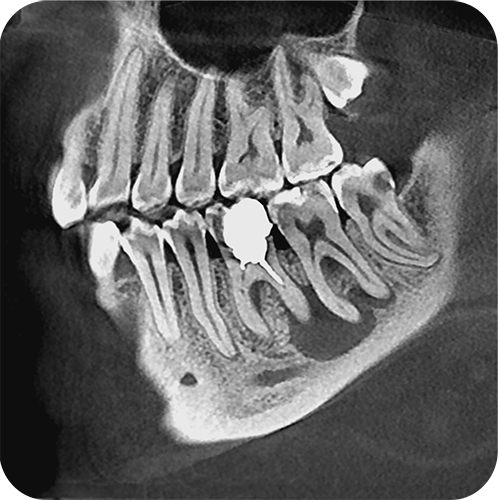

На выставке «Дентал Экспо Красноярск» успешно прошло заседание главных врачей во главе с Садовским Владимиром Викторовичем, Вице-президентом Общества Врачей России, Почетным Президентом СтАР, Директором Национального института исследований и адаптации маркетинговых стратегий (НИИАМС). Помимо насущных вопросов, руководители организаций региона обсудили преимущества и возможности использования стоматологического томографа Genoray Papaya 3D.

- Плоскопанельный детектор имеет самую высокую в классе разрешающую способность